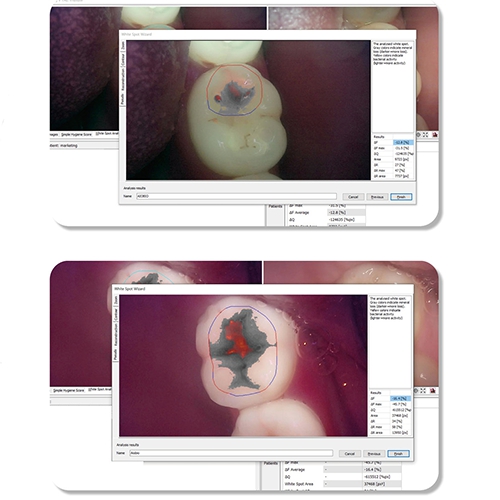

또한 병원과 환자 그리고 질병과 건강을 이어주는 구강건강관리서비스 LinkDens를 통해 치과의사 임상 판단과 AI기반 영상분석에 따른 평가와 기록을 하는 치아위험도 및 구강관리도 평가를 제공하고, 앱으로 검사결과지 확인, 예약관리, 구강상태관리를 활용하는 구강관리서비스를 신사업분야로 확장하고자 합니다.